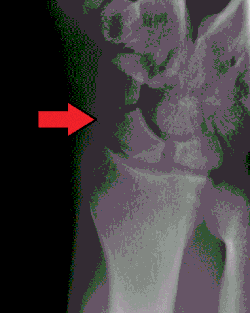

Scafoïdfractuur

Het os scaphoideum is moeilijk te breken. Desondanks is 60% van de breuken in handwortelbeentjes een breuk in het os scaphoideum. Het os scaphoideum is het minst doorbloede botje van het hele menselijke skelet, waardoor een breuk van het botje slecht geneest. Bij een scafoïdfractuur van de hand is er vaak asdrukpijn over de duim en de wijsvinger van de aangedane hand. Bovendien is de anatomische snuifdoos verstreken en drukpijnlijk.

Om de breuk radiologisch aan te tonen wordt vaak een zogenaamde navicularereeks geschoten, een serie röntgenfoto's van het os scaphoideum in vijf of zes verschillende projectierichtingen. Desondanks gebeurt het geregeld dat de breuk radiologisch niet kan worden gevonden. Het wordt na tien tot veertien dagen gipsbehandeling klinisch en zo nodig wordt het radiologisch onderzoek herhaald, omdat een breuk van het os scaphoideum soms na veertien dagen wel op röntgenfoto's is te zien.